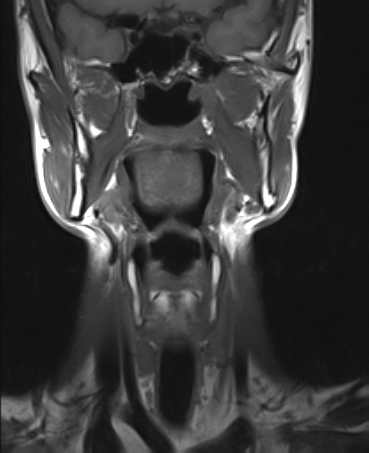

RM Partes Blandas

Prueba diagnóstica no invasiva que consiste en la obtención de imágenes de alta definición anatómica del cuello mediante el empleo de un campo electromagnético y ondas de radio (con un emisor y un receptor). No utiliza radiación ionizante. Indicaciones: sospecha de tumor, infecciones, ganglios.